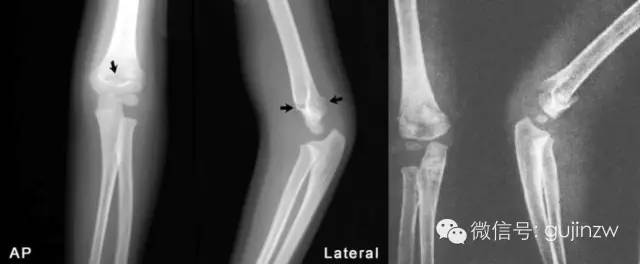

42张x线片带你读懂不同部位骨折_肱骨

图片尺寸640x264

儿童肱骨远端骨折

图片尺寸2000x2674

儿童胳膊肘骨折(肱骨髁上骨折)了怎么办? - 好大夫在线

图片尺寸610x457